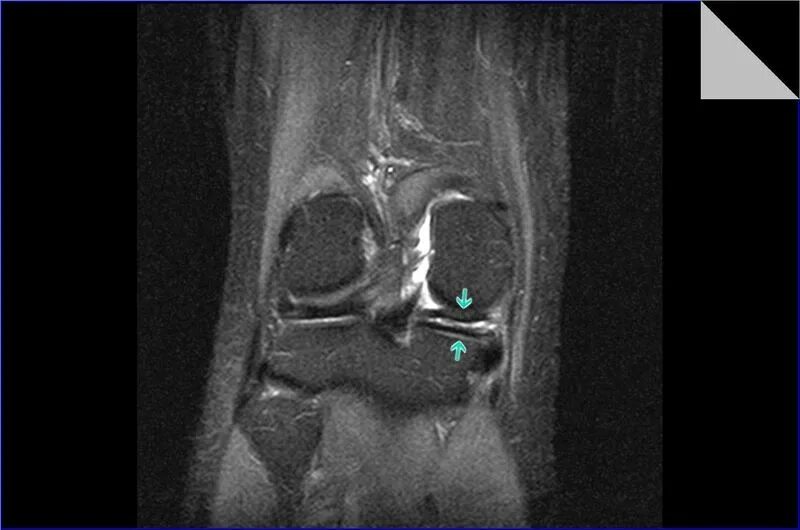

Разрыв заднего